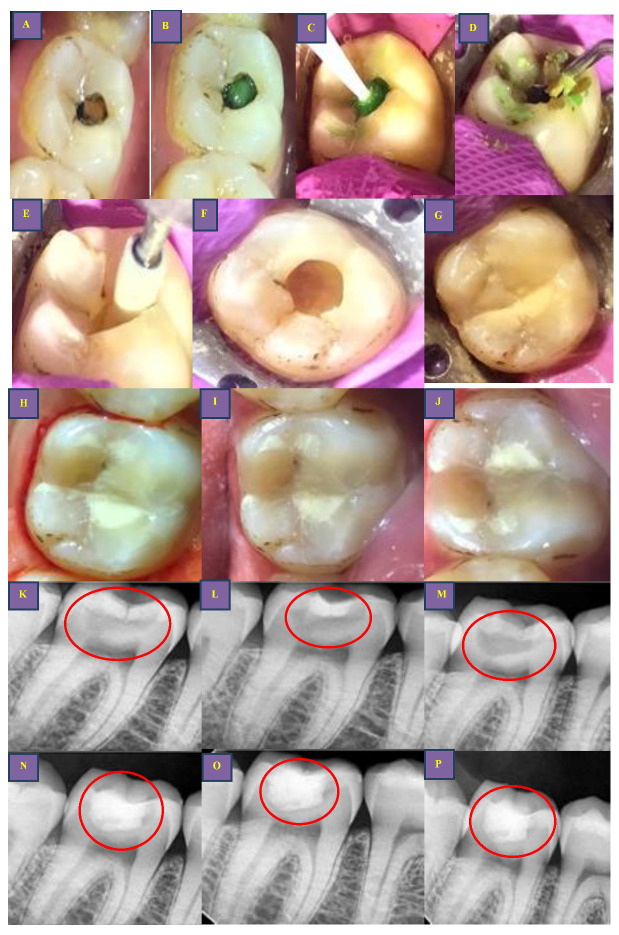

Figure 4.

Clinical steps for occlusal caries group (BCD group): (A,K): preoperative clinical photo and radiograph (red circle); (B,C,L): application clinically and extension of radiopaque BCD on radiograph (red circle); (D): caries excavation with spoon excavator and caries debris during excavation; (E): Finishing of cavo-surface margins using Arkansas stone; (F,M): final prepared cavity and post-caries excavation radiograph (red circle); (G): cavity restored with RMGIC material: (H,N): post-restoration clinical photo and radiograph (red circle) after 3 months; (I,O): post-restoration clinical photo and radiograph (red circle) after 6 months; (J,P): post-restoration clinical photo and radiograph (red circle) after 12 months.